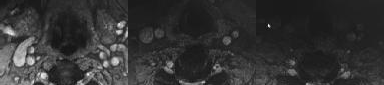

Figures 1 and 2 show sagittal and axial MRI from an 83-year-old woman with an ataxic gait, loss of dexterity, and intermittent loss of bowel and bladder control. The symptoms have been getting progressively worse over the past several weeks.

What disease process is most likely the cause of the patient’s symptoms?

4. Pigmented villonodular synovitis Discussion: B

The patient has a pannus at the C1-2 articulation that is compressing the spinal cord and causing myelopathy symptoms. The development of a pannus at this location has been associated with rheumatoid arthritis. Steinberger and associates showed increased morbidity and mortality when using an anterior approach and the surgery took longer than 4 hours. Chieng and associates showed better outcomes and lower complications rates using a posterior approach.

Question 12 of 100

CLINICAL SITUATION

When discussing anterior versus posterior surgical techniques, you counsel this patient that

Discussion: A